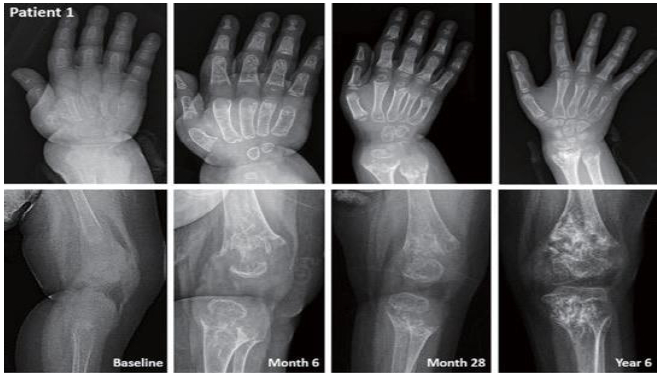

전 세계적으로 인정받는 대표적인 저인산효소증 치료법은 체내 결핍된 효소인 ALP를 피하에 직접 넣어주는 '효소 대체 요법' 주사제다. 이 치료법의 효과는 놀랍다. 5세 이하 영아 대상 연구에서 '효소 대체 요법'을 받은 영아의 1년 생존율은 95%, 5년 생존율은 82%로 이 요법을 받지 않은 대조군(각각 42%, 27%)보다 월등히 앞섰다.